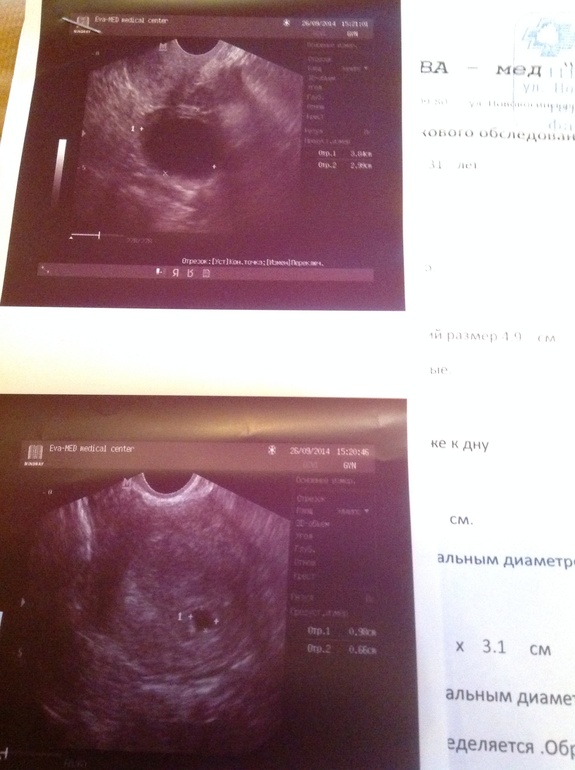

Вот фото узи

В полости матки ближе к дну ПЯ,диаметр до 8,5 мм